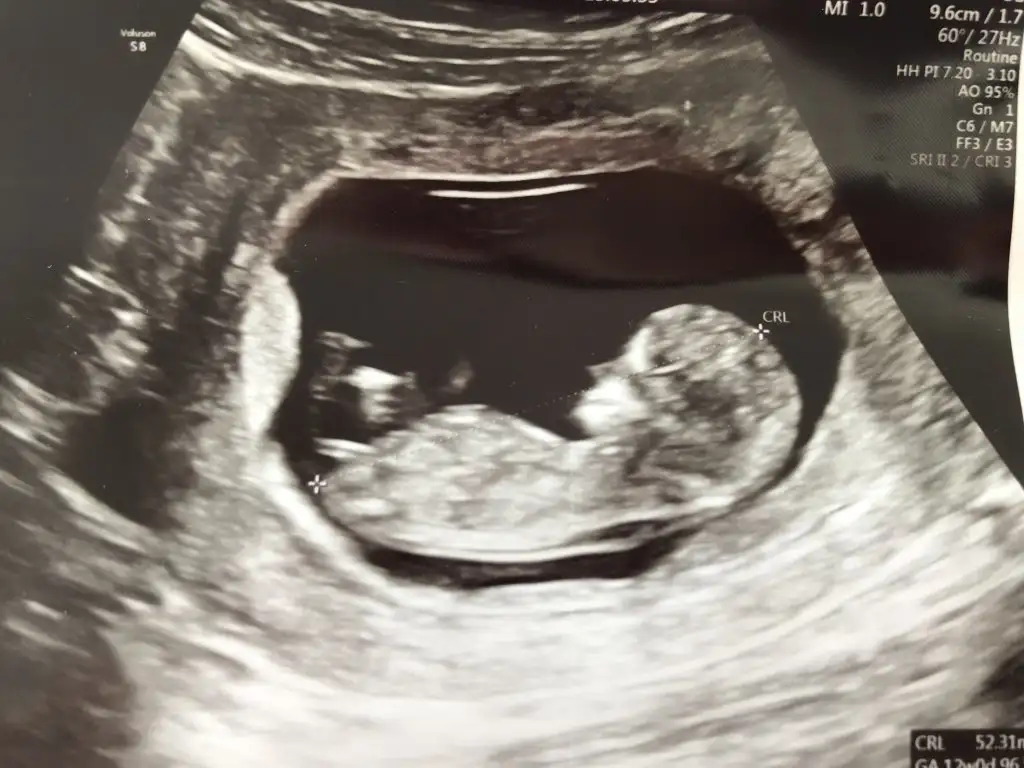

Merhaba ilki 9 haftalık son üçü 11 haftalık bir tahminde bulunabilir misiniz:)